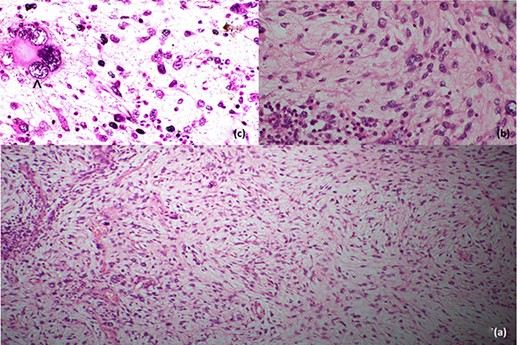

Histopathological evaluation revealed a 24 × 21 × 15 cm tumour weighing 2.645 kg (Fig. 4b) with fibrotic, solid and cystic degenerative changes without capsular infiltration or vascular invasion. There were diffuse sheets of storiform-spindle cells with variable cellularity, bizarre multilobulated and bare nuclei, eosinophilic inclusions and high mitotic activity (Fig. 5). Foci of bony metaplasia were noted in the hard area of the capsule. No adrenal tissues were identified in the entire specimen. The tumour stained immunohistochemically positive for CD68, CD99, CD34 (40%), desmin (20%) and smooth muscle actin (SMA) (10%) but was negative for Pan-CK, S100, Melan A, epithelial membrane antigen (EMA), human melanoma black 45 (HMB45), CD117, B cell lymphoma 2, chromogranin and synaptophysin (Fig. 6). No metastases were identified on screening. We referred the patient to oncology for evaluation, but they did not recommend chemotherapy, and there have been no recurrences through the 18-month post-operative period.

Histopathological features; (a) low-power image showing spindle cells in pleomorphic-storiform pattern, (b) high-power image showing spindle cells with bizarre multilobulated nuclei and (c) very high-power image depicting a nucleus in a spindle cell; the black arrowhead in (c) shows high mitotic activity in a spindle cell.

Immunohistochemical staining profile; (a) CD68-positive, (b) CD99-positive, (c) CD34-positive, (d) desmin-positive, (e) SMA-positive and (f) CD117-negative.

Detailed immunohistochemistry is needed to establish the diagnosis of PSCS of the adrenal gland. PSCS are variably positive for CD68, CD34 and CD99. Gastrointestinal stromal tumour, malignant peripheral nerve sheath tumour, malignant melanoma, synovial sarcoma, spindle cell carcinoma and pheochromocytoma are positive for CD117, S100, HMB45, cytokeratin, EMA, synaptophysin and chromogranin, respectively. Leiomyosarcoma is strongly positive for desmin, vimentin and SMA [8].